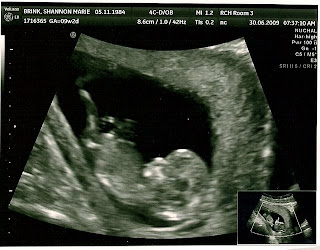

Our First Baby iBrink Sighting

Precious moments to hear the heartbeat of your baby. I was so relieved to see baby up on the screen today at our first ultrasound. I still have had a hard time belieing there really is life in my womb. I believe and trust and KNOW it was God himself who allowed this life to be forming in me but I’ve been a bit anxious to see and hear proof. Baby was a bit of a jumping bean making it hard for us to snap pictures but this is the best one. I love his/her little foot up on the wall of his/her home (my womb). So cute.